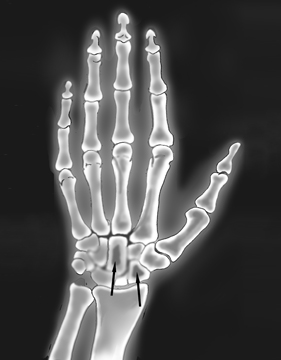

A health care provider can use urinalysis and blood tests to detect the amount of amyloid proteins in urine and blood. Imaging tests, such as x-rays and CT scans, can provide pictures of bone cysts and amyloid deposits in bones, joints, tendons, and ligaments. An x-ray technician performs imaging tests in a health care provider’s office, an outpatient center, or a hospital. A radiologist—a doctor who specializes in medical imaging—interprets the images. A patient does not require anesthesia.

X-ray image of the hand and wrist, with arrows pointing to darkened areas in two wrist bones, indicating amyloid deposits.

X-ray image showing amyloid deposits in the wrist